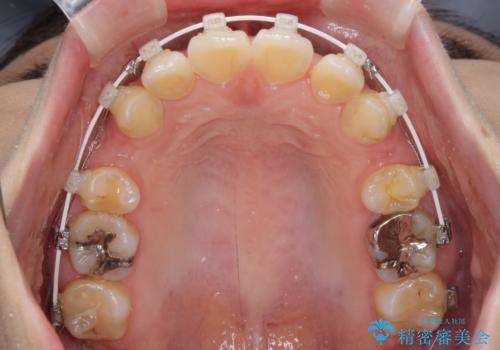

- 審美装置

上下左右第一小臼歯4本を抜歯し、ワイヤー装置にて口元を引っ込めるよう矯正治療を行うこととしました。